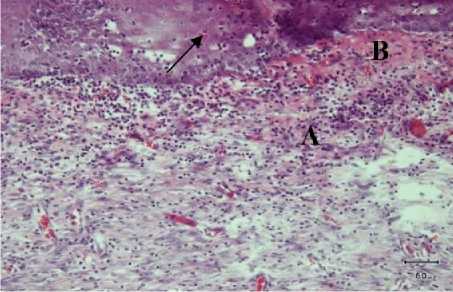

Gambar 1. Gambaran mikroskopis kulit tikus putih kelompok perlakuan I (diberi vaselin) hari ke tujuh. Terlihat adanya infiltrasi sel radang (A), proliferasi

fibroblast (B) dan neovaskularisasi (tanda panah) (HE, 100x).